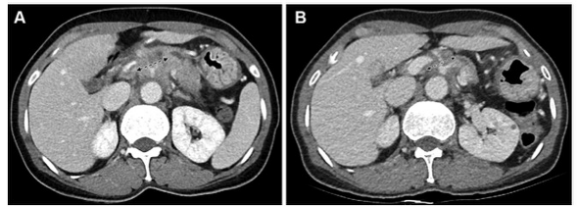

圖 患有胰腺導管腺癌的54歲女性患者的CT圖像,為第一組的代表性示例(CT和CA 19-9反應者)。(A) 基線增強CT圖像顯示胰腺體處有一個30毫米的腫塊,包繞腹腔動脈和肝總動脈(箭頭)。該腫塊為局部晚期狀態。基線CA 19-9水平為391.9 U/ml。(B)使用5-氟尿嘧啶、亮丙瑞林、伊立替康和奧沙利鉑或FOLFIRINOX一線治療8周后獲得的后續對比增強CT圖像。由于腫塊的大小略微下降到27毫米(箭頭),根據實體瘤的反應評價標準,治療反應被歸類為疾病穩定(CT反應者)。由于CA 19-9水平也降至29.2 U/mL,低于37 U/mL的臨界值,患者被歸類為CA 19-9反應者。沒有進行手術切除。在獲取數據時,該患者還生存,總生存期為44.7個月